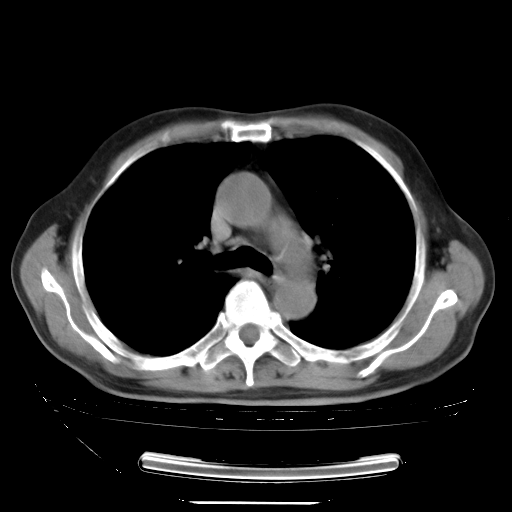

今天复查肺部CT,发现双肺广泛磨玻璃样改变。所以我把3月19日和5月9日相隔50天的肺部CT上传。请大家会诊。

2009年3月19日肺部CT片。

5月9日肺部CT(在4月27日齐鲁医院肺部CT描述部分肺组织磨玻璃样改变,12天后肺组织广泛磨玻璃样改变)